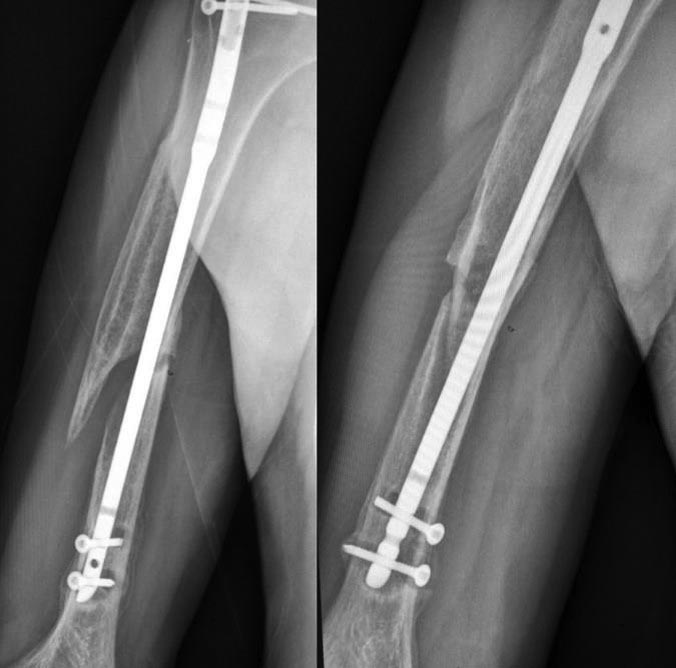

На бедре - поможет только интрамедуллярный реостеосинтез, с рассверливанием.

На плече - классическое несращение с формированием ложного сустава (все признаки нестабильности импланта). Лечить как ложный сустав исходя из ситуации. Обязательна костная пластика или другая стимуляция и восполнение дефекта. Накостным остеосинтезом лучше не пользоваться - оставшееся кровоснабжение кости будет повреждено.